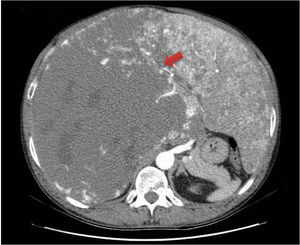

Hombre de 47 años, sin antecedentes, que consulta por dolor abdominal súbito. Se palpa hepatomegalia pétrea que ocupa ambos hipocondrios y llega hasta palas ilíacas, por lo que se realiza ecografía abdominal y posteriormente tomografía computarizada (fig. 1) con hallazgo de hepatomegalia de 37×29×23cm por lesión ocupante de espacio hepática en lóbulo derecho compatible con hemangioma cavernoso gigante. Se confirma con resonancia magnética con contraste (fig. 2), en que se objetiva que el resto del parénquima hepático está ocupado por incontables lesiones, sugerente de hemangiomatosis hepática con ausencia de parénquima hepático normal.

La hemangiomatosis hepática difusa es el reemplazo del parénquima hepático por hemangiomas, y suele asociarse a afectación sistémica2. El perfil habitual es un neonato con una masa abdominal y fallo cardíaco congestivo3. El diagnóstico en adultos sin afectación de otros órganos, como en el caso descrito, es excepcional3.